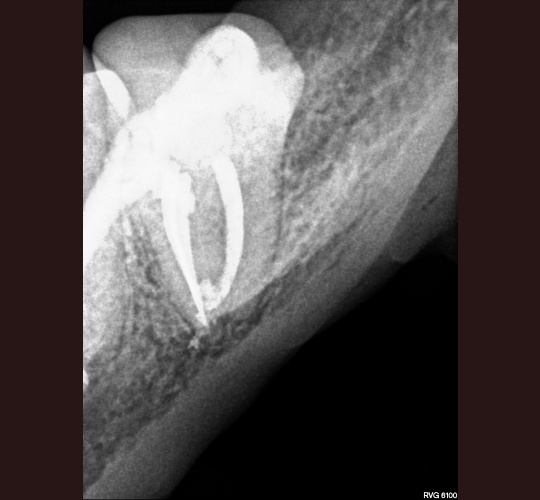

CBCT Diagnosis: Case #3

The CBCT (Cone Beam Computed Tomography) was instrumental in identifying multiple canals in this tooth. We knew from the conventional 2 dimensional radiograph that there were at least 2 roots/canals present. The CBCT showed 3 canals present. I was able to get access in all three canals and seal them.